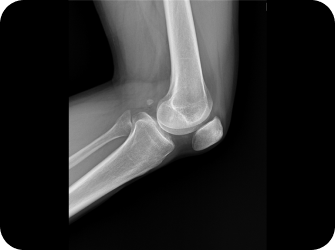

퇴행성 관절염

무릎의 퇴행성 변화로 연골 소실이 이루어져 뼈와 인대 등에 손상이 일어나 염증과 통증이 발생하는 질환으로, 노화에 의해 중년 및 노년에서 흔히 발생하며, 비만 환자나 여성에게도 주로 나타나며, 최근 30~40대 환자에게도 나타납니다.

원인

• 무릎 사용이 과다한 직업군을 가진 경우

• 유전적 요인의 경우

• 반복적인 외상이나 심한 충격으로 인한 경우

• 무릎의 퇴행성 변화로 연골이 닳아진 경우

• 무릎관절의 과다 사용인 경우